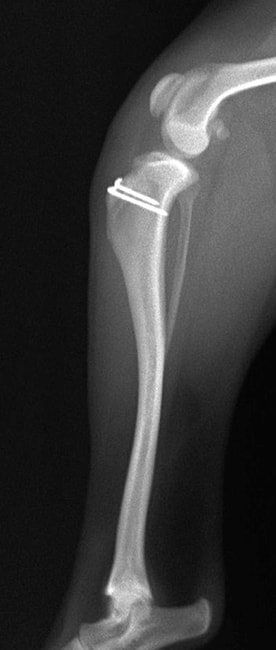

■ 症例24 キャバリア 7か月

左右膝蓋骨内方脱臼(左:グレードⅣ 右:グレードⅢ)

以前から左右後肢の跛行が認められ、整形外科学的検査・レントゲン検査により左右の膝蓋骨脱臼が認められた。症状が重度である左膝の膝蓋骨脱臼整復術を行った。外科手技は縫工筋及び内側広筋の解放、脛骨粗面の外側転位、滑車ブロック形造溝術、内外側関節方の縫縮を実施した。術後一か月時点で、左の膝蓋骨は安定しており経過は良好である。

本症例は成長期における重度の膝蓋骨脱臼であり、術後の再発の可能性もあるため、経過をしっかりと観察していく必要がある。また、今回手術を実施していない右膝に関しても経過を観察し、手術を検討していくこととする。